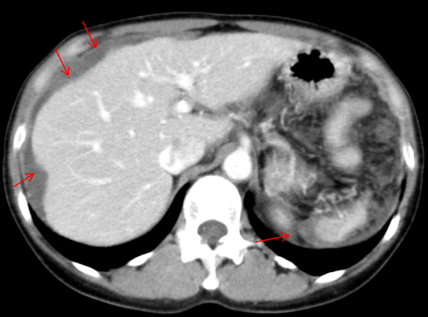

• ホタテ貝状変形

肝臓や脾臓(ひぞう)の表面がでこぼこと波打った状態を指し、粘液であることを示唆しています。

ホタテ貝状変形の様子